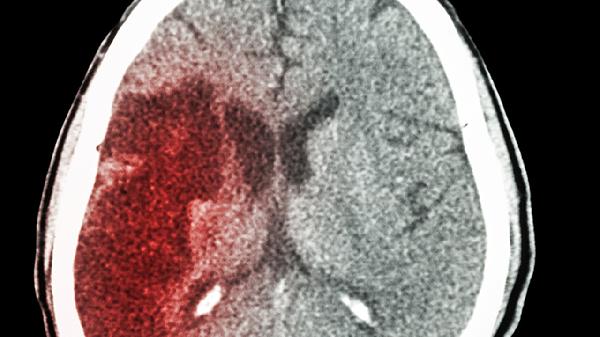

左脑和右脑在功能上存在明显差异,左脑主要负责逻辑思维、语言表达和数学运算,右脑则主导空间感知、艺术创造和情感处理。这种分工被称为大脑功能偏侧化,但两者通过胼胝体紧密协作,共同完成复杂认知活动。

虽然存在功能偏侧化,但健康人的大脑两侧始终保持协同工作。例如语言理解需要右脑辅助处理语调变化,而空间任务也需要左脑参与逻辑分析。大脑损伤后的功能重组也证明了两侧半球具有可塑性,儿童期脑损伤后未受损区域可能代偿部分功能。